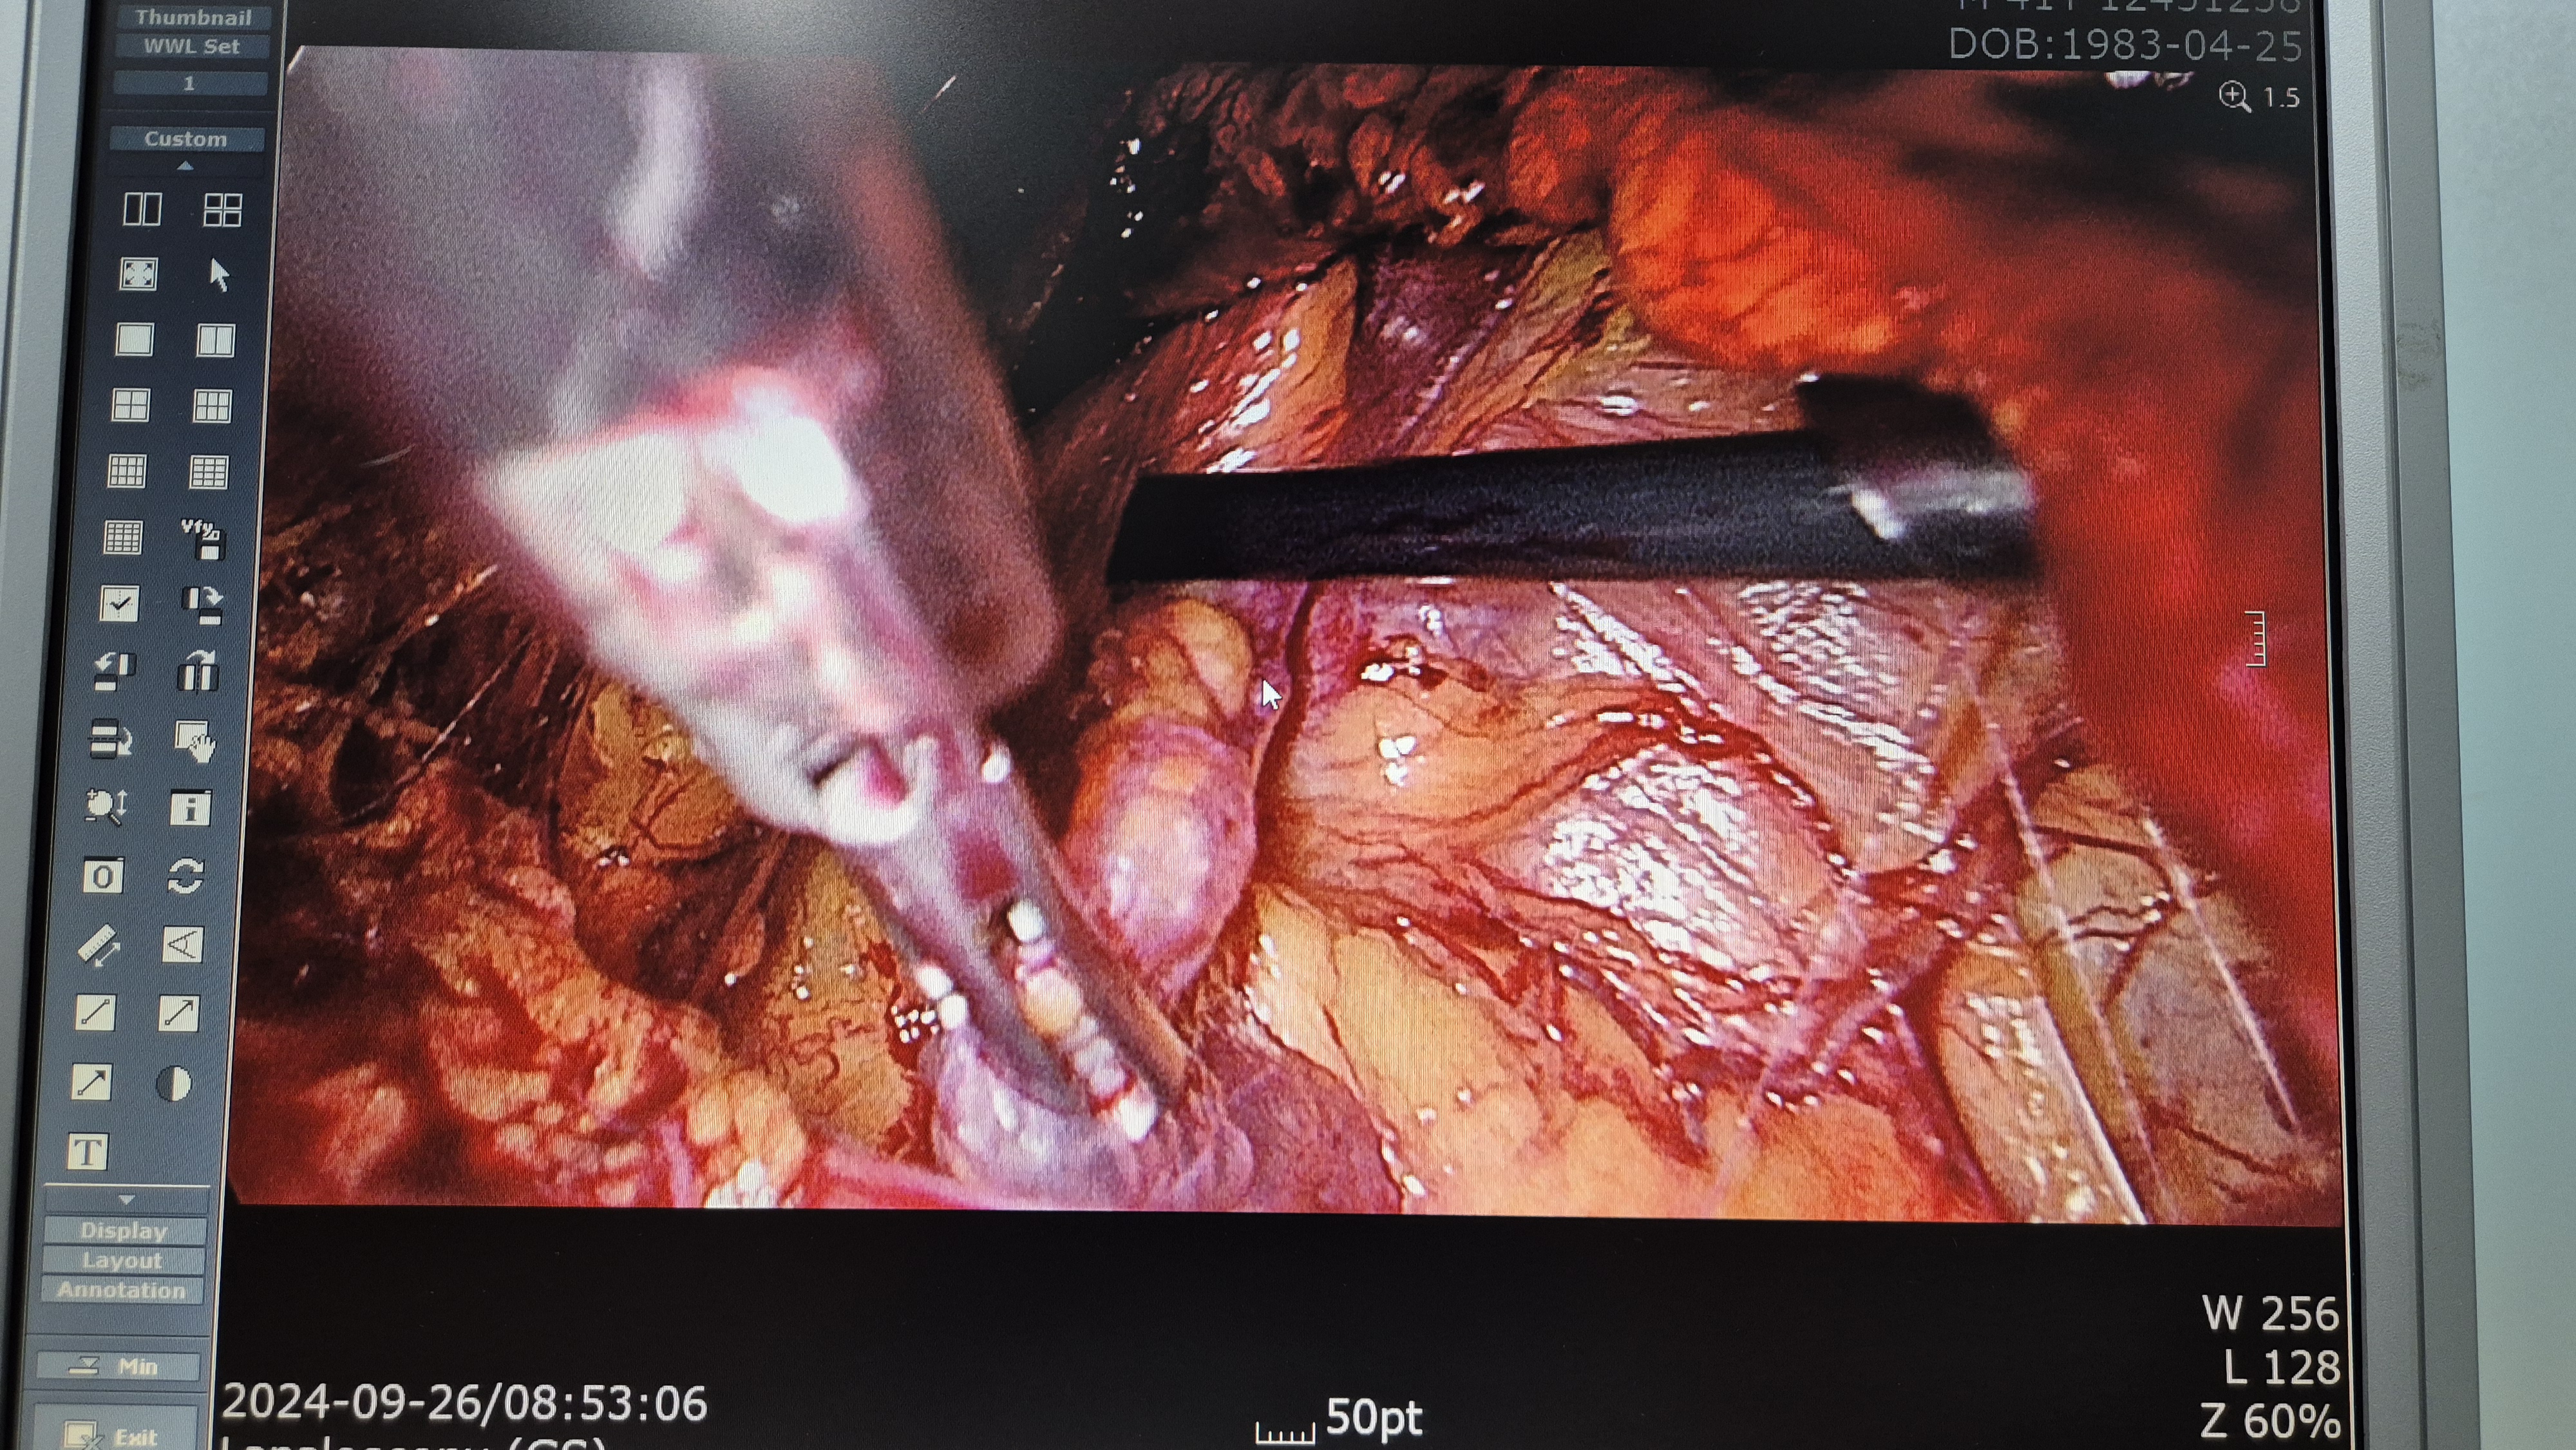

우측 서혜부 종물 주소로 내원하여 초음파 시행후 서혜부 탈장으로 확인되었고 배꼽탈장도 있었습니다,

방금 복강경 탈장교정술 및 배꼽탈장 교정술을 시행했습니다.

수술은 20분 걸렸습니다.